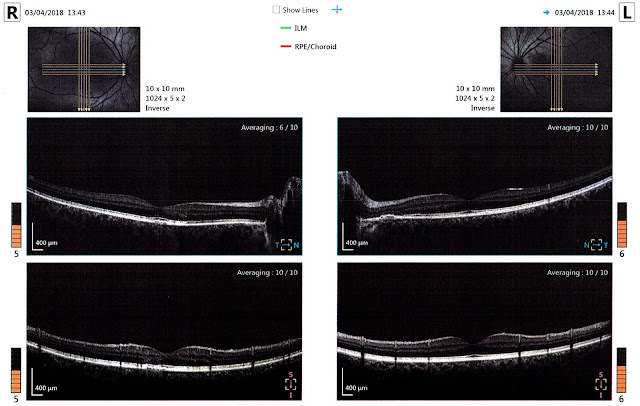

What evidence is there that this might be my problem? I'm glad you asked. Here's part of the OCT scan taken of my retinas at my ophthalmology appointment in April:

Ok, so maybe you don't know how to read one of these. I already had some idea since doing some research after my first OCT years ago, but reading this page helped enormously—go read it if you're interested in more detail than I talk about here.

- These images are ‘standard’ medical imaging, so my left eye is on the right, and my right eye is on the left.

- The small thumbnails at the top are retinal photos with lines indicating how the machine scanned my eyes. The middle row is a horizontal scan (cyan arrow in thumbnail). The lower row is a vertical scan (magenta arrow in thumbnail).

- N/T in the middle row is Nose/Temple. Looking left to right, the right eye scan goes from temple (side of face) to nose (middle), then the left eye scan from nose (middle) to temple (side). The centre of the page shows the head of the optic nerve, corresponding to the blind spot. When you look for it in your vision, the blind spot appears towards the outside from the centre, but remember the image on your retina is inverted; the nerve is actually closer to your nose.

- Similarly, S/I in the bottom row is Superior/Inferior, ie. top/bottom. That is, the top of the retina is on the left in the scan, and the bottom on the right. Again, remember that this is the opposite of what you see: the top of your retina sees the bottom of your vision, and vice versa.

- Finally, the dip in the middle of each scan is the fovea. The centre of your vision has much higher resolution (actually ‘acuity’), meaning many more light detecting cells. The shape of the retina here is to make room for this.

The highlighted sections (and maybe also the bit with a dimmer highlight) correspond approximately with where I see visual issues in my left eye, out from the centre towards the blind spot. The left-most section highlighted here certainly looks to me (a non-expert) like the OCT examples for RPE CSR from this page I linked to above.